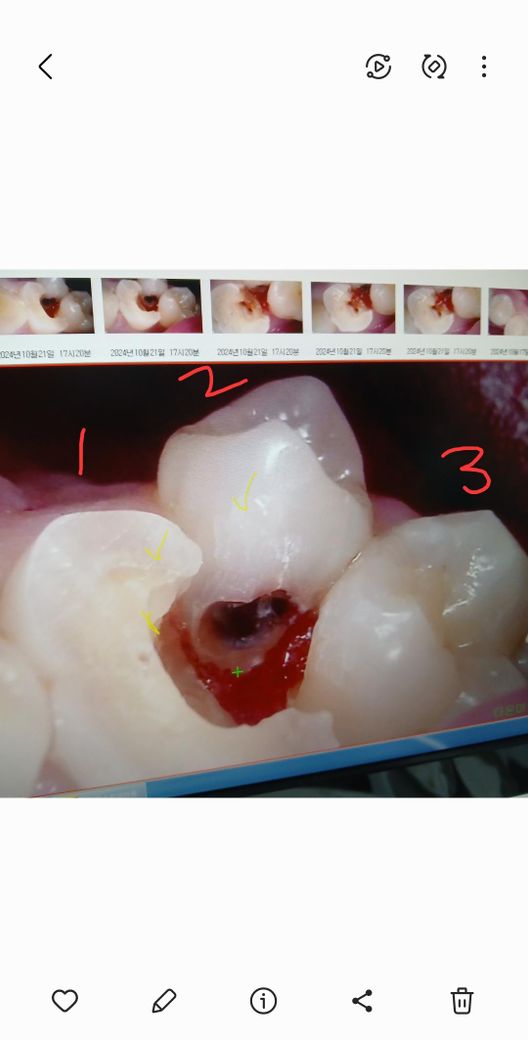

1,2번사진속 1번치아를 신경치료 중인데

보기에는 충치도없는거 같고 통증도

전혀 없었습니다 삼각형 부위에 음식물이

잘 끼기는 했어요

그래서 그런지 그곳을 중심으로 인접한

치아들에 충치가 생겼다고

1번은 신경치료후 지르코니아

2번은 과잉치로 발치

3번은 인접면만 레진 한다고 합니다

2번3번은 수긍이 가는데

1번은 아무런 증상이 없는데 꼭 신경치료를

했어야 했는지 또 치아를 너무 많이 갈아낸거아닌지 의문입니다

객관적으로 일반적인 치료인지 확인부탁드립니다

사진으로 봤을경우 1번치아는 충치가 깊게 진행되어 있는 것으로 보입니다.

충치를 제거하고 신경관에 노출이 되거나 신경관에 감염이 있을것으로 예상될 때는 신경치료가 필요할 수 있습니다.